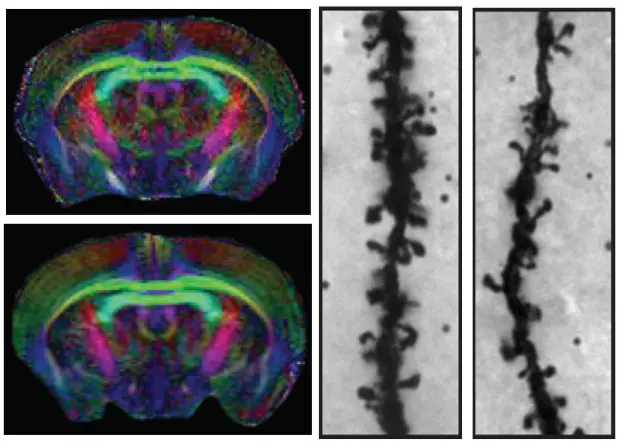

We have recently shown how several genes encoding proteins belonging to the nerve growth inhibitory Nogo signaling system are regulated to influence structural synaptic plasticity and the formation of lasting memories. Ongoing studies using transgenic animals aim at understanding molecular mechanisms behind the formation of lasting memories and causes of memory disorders, as seen e.g. in aging.

Overexpression of Nogo receptor 1 (NgR1) in forebrain neurons does not affect gross brain anatomy but inhibits the formation of dendritic spines.